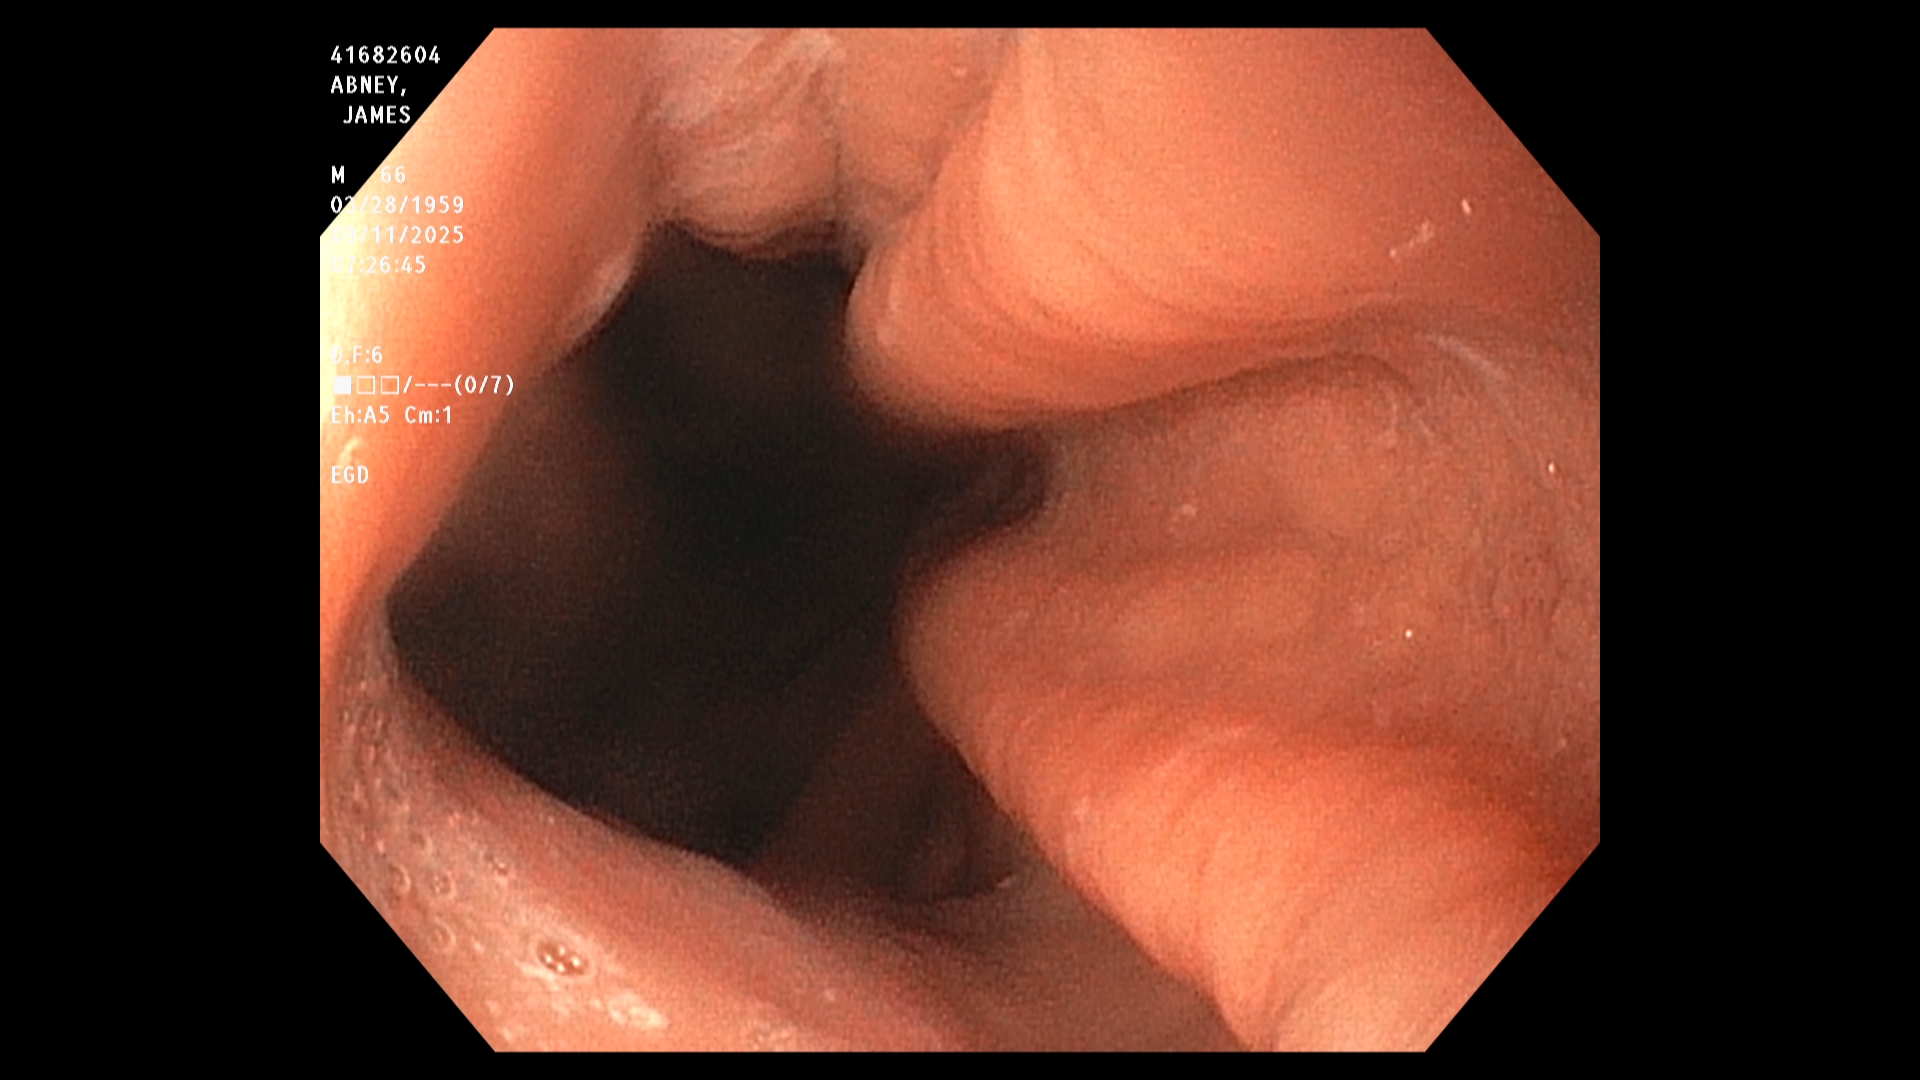

The endoscopist in this study generated a series of images showing the stomach, duodenum,

duodenal bulb, and esophagus, among others. The stomach was imaged first. The image is a

retroflexed view, in which the endoscope was passed through the stomach and the camera

turned backward to take the image, which shows both the stomach and an upstream portion of

the endoscope. The endoscope was next passed into the duodenum, farther down the GI tract,

and then withdrawn while care was taken to observe mucosal detail.